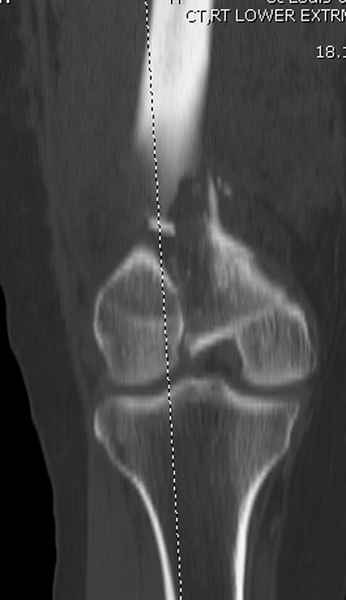

При наличии различных имплантов, любые варианты: слева (полу) открытым - мининвазивным, а справа закрытым интрамедуллярным методом, его считаем более чем приемлемым для фиксации данных переломов.

Проксимальная и дистальная блокировка, независимо от техники введения штифта, ретроградно или антеградно, гарантирует сращение сегментарных переломов бедра без укорочения. Штифты диаметром 12 мм с блокировкой сверху и вниз двумя шурупами выдерживают вес 75 кг больного, что позволяет раннюю профилактику контрактур.

Погоня за "красивой рентгенограммой" не всегда оправдана для фиксации кости, где имеется массивное мягкотканое покрытие. Если так уж хочется исправить положение кости, то при наличии ЭОП, большие костные фрагменты могут быть развернуты или приближены к основному фрагменту методом применения Joystick.

Главное в лечении сегментарных переломов - необходима осторожность при рассверливании канала, продвижение гибкого сверло через сегмент проводят без сверления, толканием, а то были случаи, когда весь сегмент крутился вместе со сверлом.